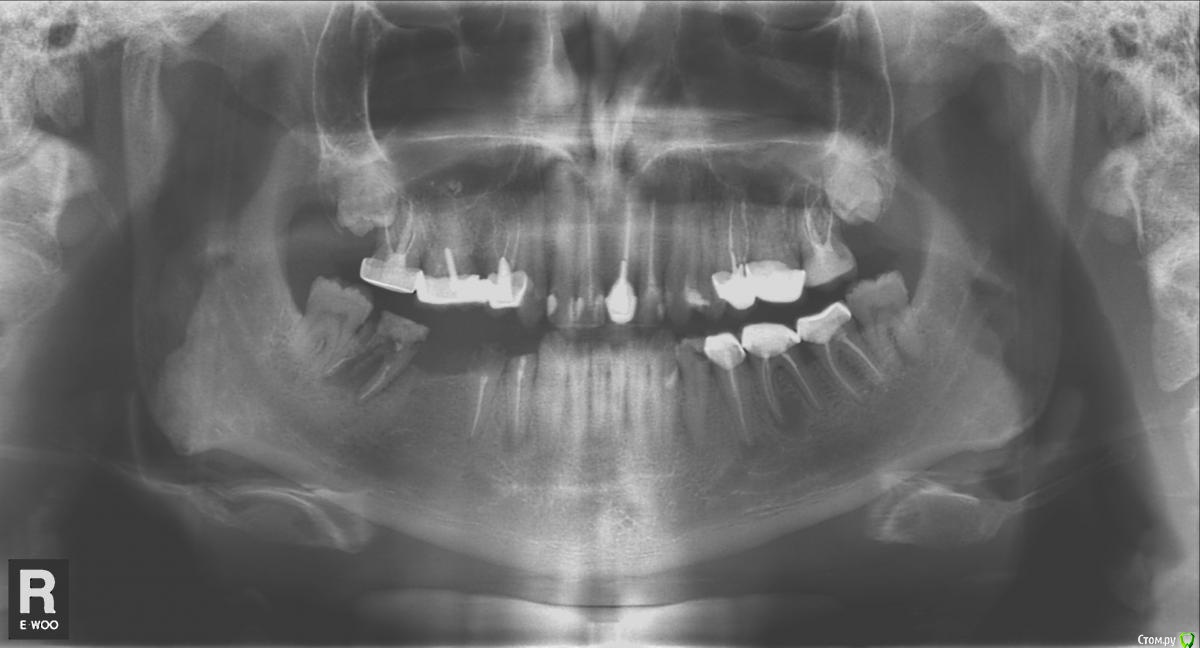

feoddor Опубликовано 6 февраля, 2019 Поделиться Опубликовано 6 февраля, 2019 (изменено) Добрый день. Прошу помощи,совета т.к. сил моих уже больше нет.Мне 35 лет, и всю свою сознательную жизнь я лечу зубы. Не очень успешно(Текущая острая проблема:Снизу,справа стоял мост 5-7.Но в семерке обломилась вкладка, семерку с огромным трудом удалось спасти , и восстановить на стеклокерамических штифтах.Депульпировал здоровую 5-ку,поставил новый мост: 4+5->7Вчера он вывалился.Простоял 4 года. Но за эти 4 года у меня там выросла вполне себе визуально полноценная восьмерка.Что теперь делать? Снимок сделал, вот думаю, куда идти сдаваться. С 7-ой, похоже - все, конец. Или стоит опять что-то попытаться сделать? 5 и 4 визуально выглядят плохо,+ они чуть побаливали эти 4 года. + там вижу какое то потемнение у корня 4-ки( Она обломилась,кусок остался в коронке. 8-ка здоровая, не беспокоит. Удалять ее вообще не хочется(если связываться с имплантами), но и как использовать ее - не знаю. Имеет ли смысл рассматривать мост 8-4+5? Обязательно ли в этом случае депульпировать восьмерку? У меня маленький рот,сводит судорогами челюсть, если держать сильно открытым. И депульпация восьмерки , скорее всего, превратится в тот еще ад. И не факт, что при этом удастся нормально пройти все каналы в ней, а я слышал, что там с ними все сложно. Может попробовать поставить на нее мост без депульпации, комбинированный:штамповка + МК? Мне эта идея на данный момент больше всего нравится. Нужно ли перелечивать 4-5? Или вообще все удалять и ставить мост на имплантах....но это вообще - абзац. И по времени, и по финансам, и с эстетической стороны(((( Прошу помощи, совета. Прилагаю свежий снимок.Зараннее спасибо. Изменено 6 февраля, 2019 пользователем feoddor Ссылка на комментарий

red_butler Опубликовано 6 февраля, 2019 Поделиться Опубликовано 6 февраля, 2019 Что теперь делать? 4.8 4.7 4.5 удалять Имеет ли смысл рассматривать мост 8-4+5? нет У меня маленький рот,сводит судорогами челюсть, если держать сильно открытым. лечитесь под седацией Или вообще все удалять и ставить мост на имплантах....но это вообще - абзац это не так страшно ))) Ссылка на комментарий

feoddor Опубликовано 7 февраля, 2019 Автор Поделиться Опубликовано 7 февраля, 2019 (изменено) Спасибо, к тому все и идет.... 4.8 4.7 4.5 удалять А можно узнать, чем вам 4.5 не понравился? На 4.4 - вообще гранулема, судя по снимку. А восьмерку то за что? Но всякий случай? Изменено 7 февраля, 2019 пользователем feoddor Ссылка на комментарий

red_butler Опубликовано 7 февраля, 2019 Поделиться Опубликовано 7 февраля, 2019 Спасибо, к тому все и идет.... А можно узнать, чем вам 4.5 не понравился? На 4.4 - вообще гранулема, судя по снимку. А восьмерку то за что? Но всякий случай?Оставшийся объём твёрдых тканей не позволяет его восстановить. 4.4 под большим вопросом, если пойдёт под коронку, то его нужно перелечить.4.8 лишён антагониста (нет восьмерки сверху), и частично сместился, если не хотите проблем в будущем, то отпустите его Ссылка на комментарий